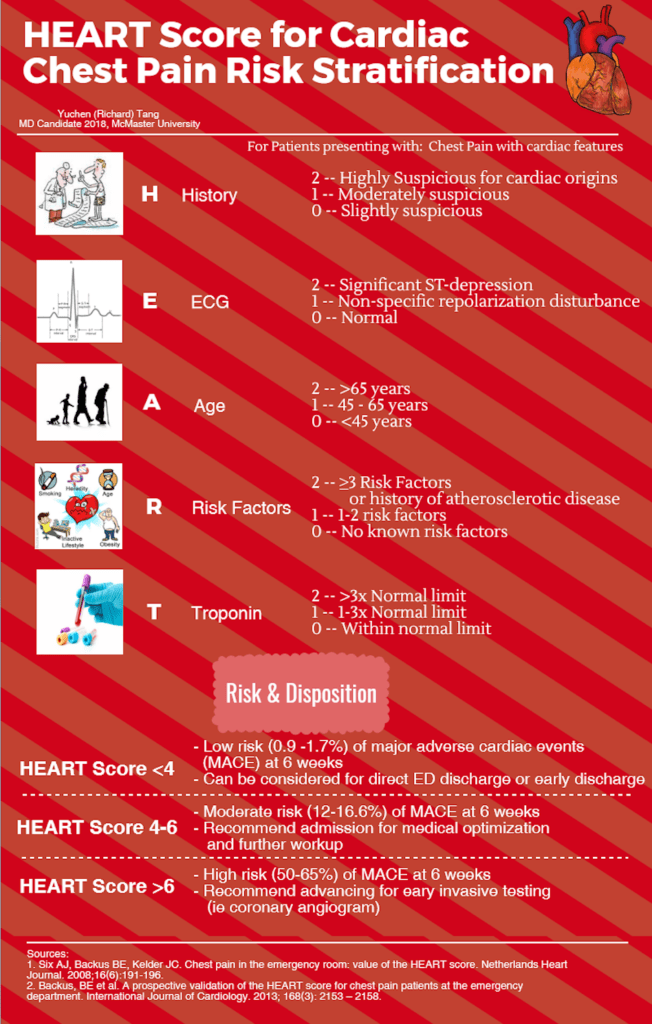

The HEART score is an excellent tool that can be used in the ED setting to prognosticate and triage patients with possible Acute Coronary Syndrome (ACS) for admission for further workup and treatment versus safely discharging home with follow-up instructions. The scoring system is based on expert opinion and validated in several ED populations worldwide. 1 2 Most importantly, the scoring system focuses on disposition via calculating the risk of a Major Adverse Cardiac Event (MACE) within 6 weeks. 1 The HEART score is highly practical for the ED to help focus on identifying low risk as well as high risk patients, in order to offer appropriate care and disposition as early as possible.

The HEART score comes with an inherent mnemonic of HEART (free of charge), making it easy to remember and use.

The HEART score is a well validated ED clinical decision tool that helps prognosticate and triage patients who present with chest pain suspicious for cardiac features. It identifies patients who are either already sick or at risk of becoming sick by estimating risk of MACE within 6 weeks of presentation to ED. It also helps identify patients who should stay in hospital for further cardiac workup and those who may be safely discharged due to minimal risk of MACE. It is easy to remember as each letter of the HEART score stands for a component of the heart score – History, ECG, Age, Risk factors, Troponin. Take this HEART score to heart when evaluating patients with possible acute heart problems!